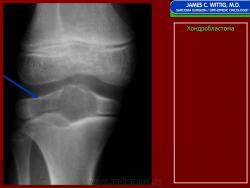

Хондробластома — это редкая доброкачественная опухоль, локализующаяся, главным образом, в эпифизе и отличающаяся своеобразным клеточным составом. Ткань новообразования представлена овальными, округлыми и веретеновидными клетками, напоминающими незрелые хондроциты (хондробласты). Зрелый гиалиновый хрящ определяется лишь в некоторых опухолях. Возраст больных варьирует. Мужчины поражаются в два раза чаше женщин. Пациенты предъявляют жалобы на боли в течение нескольких месяцев или лет, у некоторых больных определяются внутрисуставной выпот, припухлость и ограничение движений. Наиболее типичная локализация опухоли — проксимальные эпифизы плечевой и большеберцовой костей, а также дистальный эпифиз бедренной кости. У 20 % больных опухоль развивается в плоских или коротких трубчатых костях, преимущественно в пяточной и таранной. Изредка поражаются кости лицевого черепа, в том числе височная. В большинстве случаев новообразование выходит за пределы эпифиза и распространяется на метафиз. На фоне остеолиза обнаруживаются рассеянные участки обызвествления в виде пунктирных линий, а также разреженный трабекулярный рисунок. Хондробластома, как правило, не выходит за пределы кости, но изредка проникает в полость сустава. В процессе роста опухоли иногда возникает вторичная аневризматическая костная киста.

Рентгенологически хондробластома представляет собой сравнительно большой (2-4 см) очаг округлой формы, четко отграниченный от окружающей кости склеротической каймой. На фоне очага в большинстве случаев, но не обязательно определяются плотные включения, напоминающие хлопья ваты.

Рентгенологическая картина. Хондробластома выглядит как небольшой, от 3 до 6 см литический очаг, центрально или эксцентрично расположенный, с четкими контурами, занимающий около половины площади эпифизарной зоны. Хондробластома плоских костей и мелких трубчатых костей больших размеров, может сопровождаться припухлостью мягких тканей, вздутием кости и периостальной реакцией. Распространение процесса на метафизарную зону встречается часто.